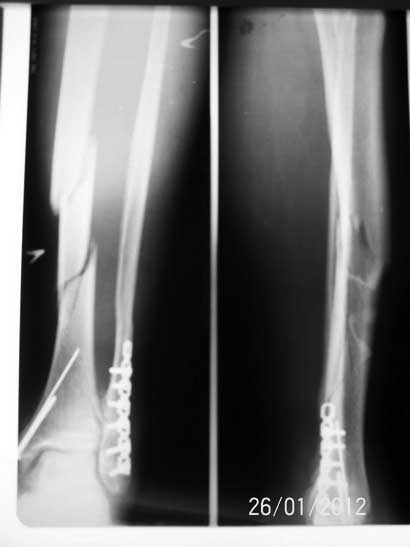

Спасибо всем откликнувшимся! Докладываю результат. Свищ после удаления лигатуры за неделю затянулся. Фиксаторы с лодыжек удалены, БИОС. Мы удовлетворены, пациент доволен.

1. Снимок датирован 260112 (как исходный так и послеоперационный)

Ув. Андрей! Это не было желанием похвалиться. Это было желание услышать мнение незаинтерисованных коллег. Просто нам было настойчиво рекомендовано оперировать открыто пластиной. Хотелось узнать найдет ли кто в данной ситуации преимущества использования пластины перед БИОС, мы таки не нашли - и вот результат.

И перелом это не "фрагментарный", т.е. оскольчатый, а "сегментарный", т.е. двойной.